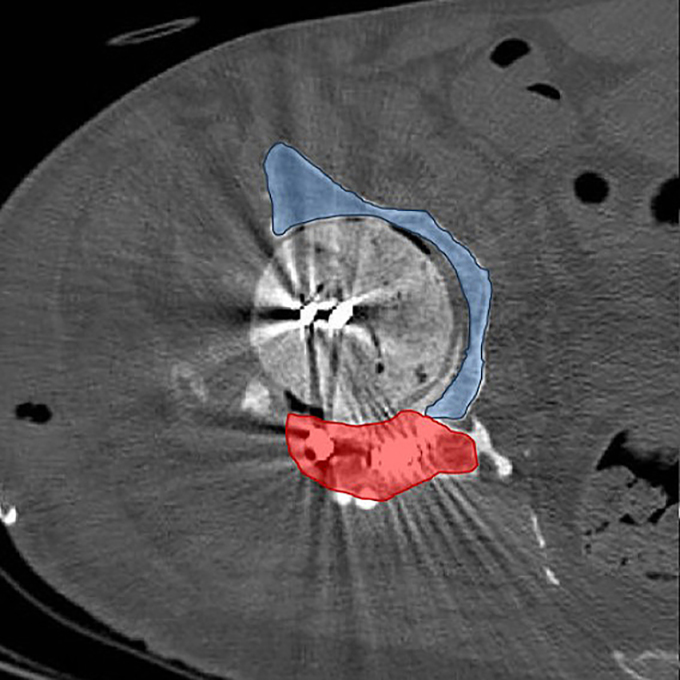

Axial CT image illustrating temporary posterior wall (red) and residual bone stock (blue), explaining multidirectional instability.

During reimplantation, removal of the spacer and prior tectoplasty exposed a Paprosky IIIA acetabular defect. A complete posterior wall deficiency combined with a significant superior acetabular roof defect resulted in translational instability of the trial component in both cranio-caudal and anteroposterior directions. Cranio-caudal stability was achieved using a cranial trabecular titanium augment (TrabecuLink Augments). However, anteroposterior instability persisted.

The decisive step in reconstruction was the mechanical integration of a PPR-type acetabular cage with the trabecular titanium augment. The flanges of the MobileLink PPR were connected directly to the augment using 4.5 mm screws, transforming two independent components into a unified structural construct.

This integrated configuration restored stability in both planes and allowed early full weight-bearing.